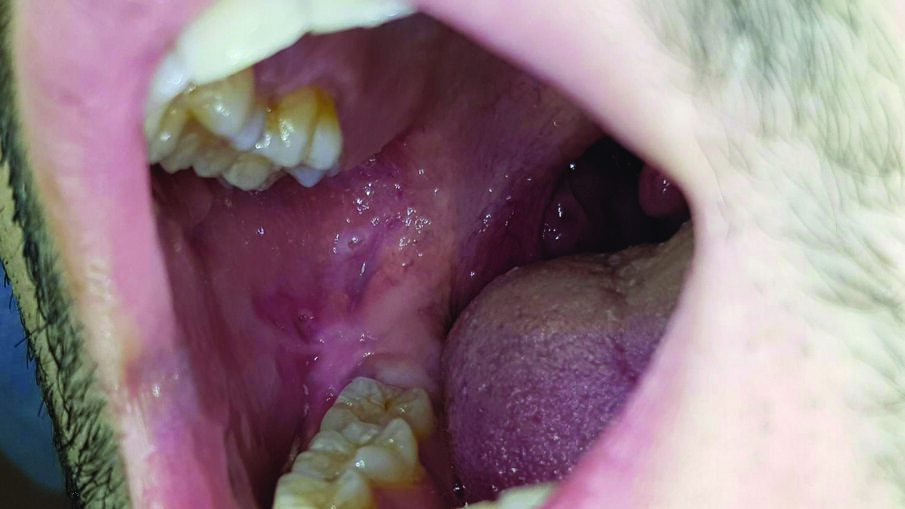

Caso clinico I

Un paziente di 27 anni sottoposto a una visita di controllo, presenta nel cavo orale a livello della mucosa buccale destra un’afta minor sintomatica, soprattutto quando viene a contatto con il cibo o sostanze liquide. Il paziente ci riferisce che qualche giorno prima di venire alla visita di controllo aveva contratto una sindrome influenzale (Fig. 1). Si prescrive collutorio a base di olio di oliva ozonizzato (Ialozon, Gemavip, Cagliari, Italy) da utilizzare puro come sciacquo orale per 1 minuto ogni 8 ore per 5 giorni e GEL con olio di oliva ozonizzato arricchito con aloe e acido ialuronico (Ialozon gel orale, Gemavip, Cagliari, Italy) 3 volte al giorno per 5 giorni. Dopo 5 giorni la lesione aftosa era completamente regredita (Fig. 2).

Fig. 1 - L’afta minor nella mucosa buccale destra.